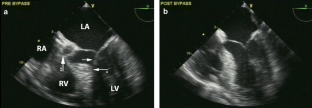

Fig. 1